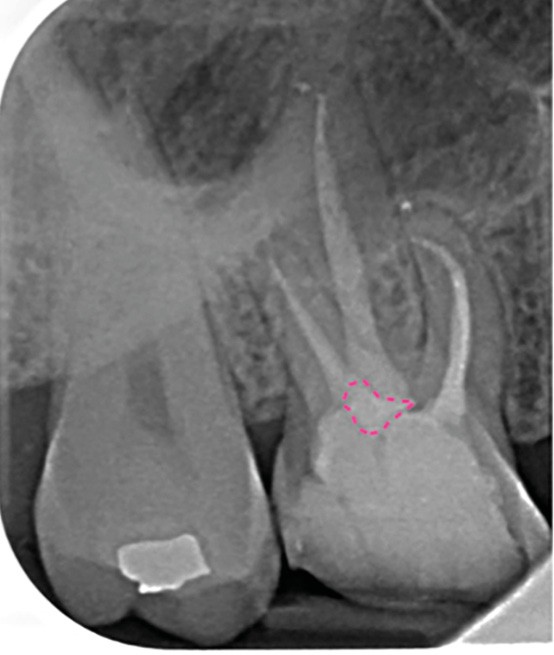

Perforation infra-osseuse avec accès visuel direct (fig. 3)

Ce type de perforation est également la plupart du temps iatrogénique et survient lors de la recherche ou de la mise en forme canalaire, lors de la préparation pour un logement de tenon radiculaire. Situées au niveau du plancher pulpaire des dents pluriradiculées, ou au niveau des entrées canalaires des dents monoradiculées ou pluriradiculées, il s’agit le plus souvent de perforations à quatre parois. Si la perforation survient en cours de traitement, elle doit être gérée immédiatement pour un meilleur pronostic (fig. 4). Néanmoins, il est important de prendre en compte l’épaisseur résiduelle du plancher. Si le plancher est trop fin, il ne sera pas possible d’envisager de traiter la perforation.